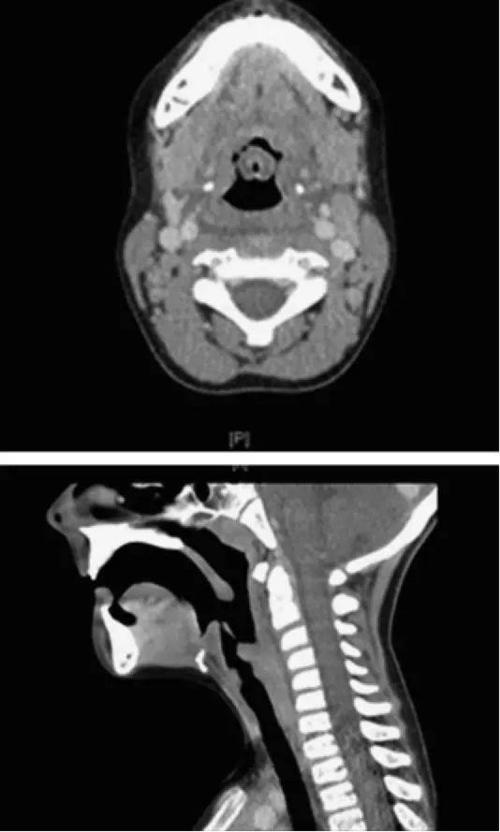

ct示:会厌明显肿胀,增粗,密度减低,咽腔狭窄男,50岁,3天发热,咽痛

ct(轴位结合矢状位)显示会厌和杓会厌皱襞弥漫水肿和软组织肿胀